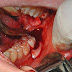

Lấy tủy răng là gì? Mất bao lâu?

Có nên lấy tủy răng không? Lấy tủy răng mất bao lâu thời gian? Tất cả đều được giải đáp qua bài viết sau đây của chúng tôi. Hãy cùng theo d...